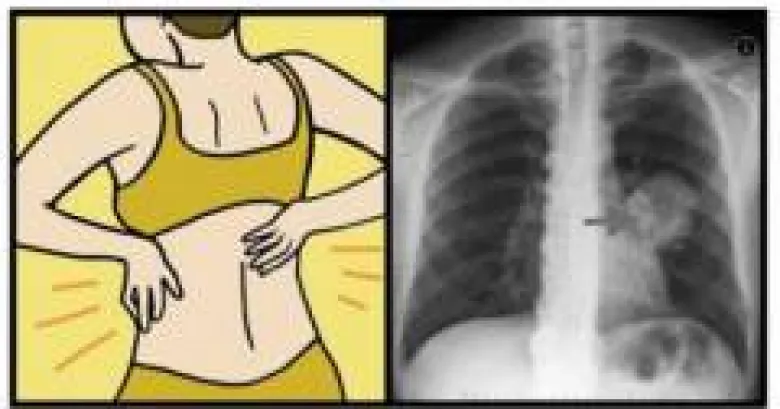

Քաղցկեղը որոշակի նշաններ չունի, սակայն որոշ ախտանշաններ կարող են այնուամենայնիվ վկայել քաղցկեղի առկայության մասին:

Այդպիսի նշաններից են.

Արյունահոսությունը կամ արտադրությունը

Գլխապտույտը

Ջերմաստիճանի անբացատրելի բարձրացումը: Մաշկային ծածկույթի փոփոխությունները

Արտազատական համակարգի գործառույթների խանգարումը: Տևական ապաքինվող վերքը կամ խոցը: Գորտնուկների կամ խալերի փոփոխությունները: